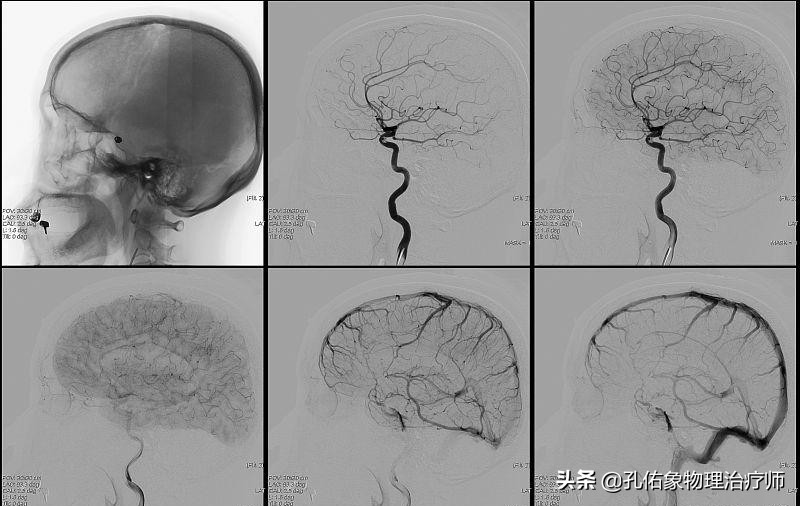

- 医生会详细咨询病史,查体及结合影像等综合判断您的问题是不是脑梗?是哪一种类型的脑梗?选择什么样的治疗方式?

②在发病早期(3-6小时内),首选药物来溶栓治疗,效果佳;若是药物疗效不佳,可进行介入取栓治疗。